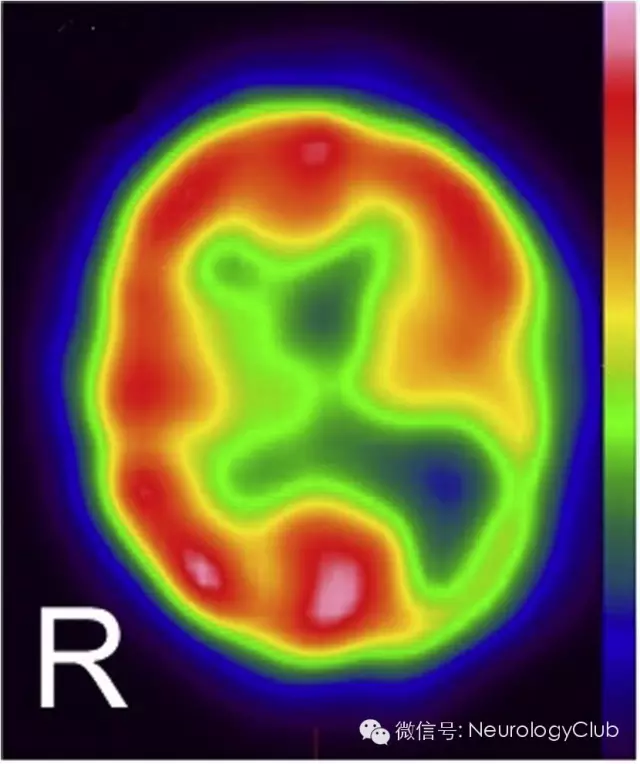

(图2:锝-99m SPECT灌注扫描)

MRI黑水像(图1A)可见双侧顶枕区不对称的异常高信号。相应的DWI(图1B)上可见病灶弥散受限,而ADC呈低信号(图未放),提示右侧顶枕区急性梗死,而左侧顶枕区应为先前梗死病灶。锝-99m SPECT灌注扫描可见左侧顶枕区灌注缺损(图2)。